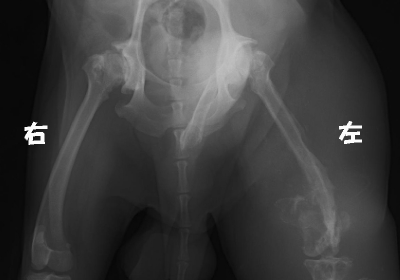

デジタルレントゲン あいむブログ あいむ動物病院 西船橋